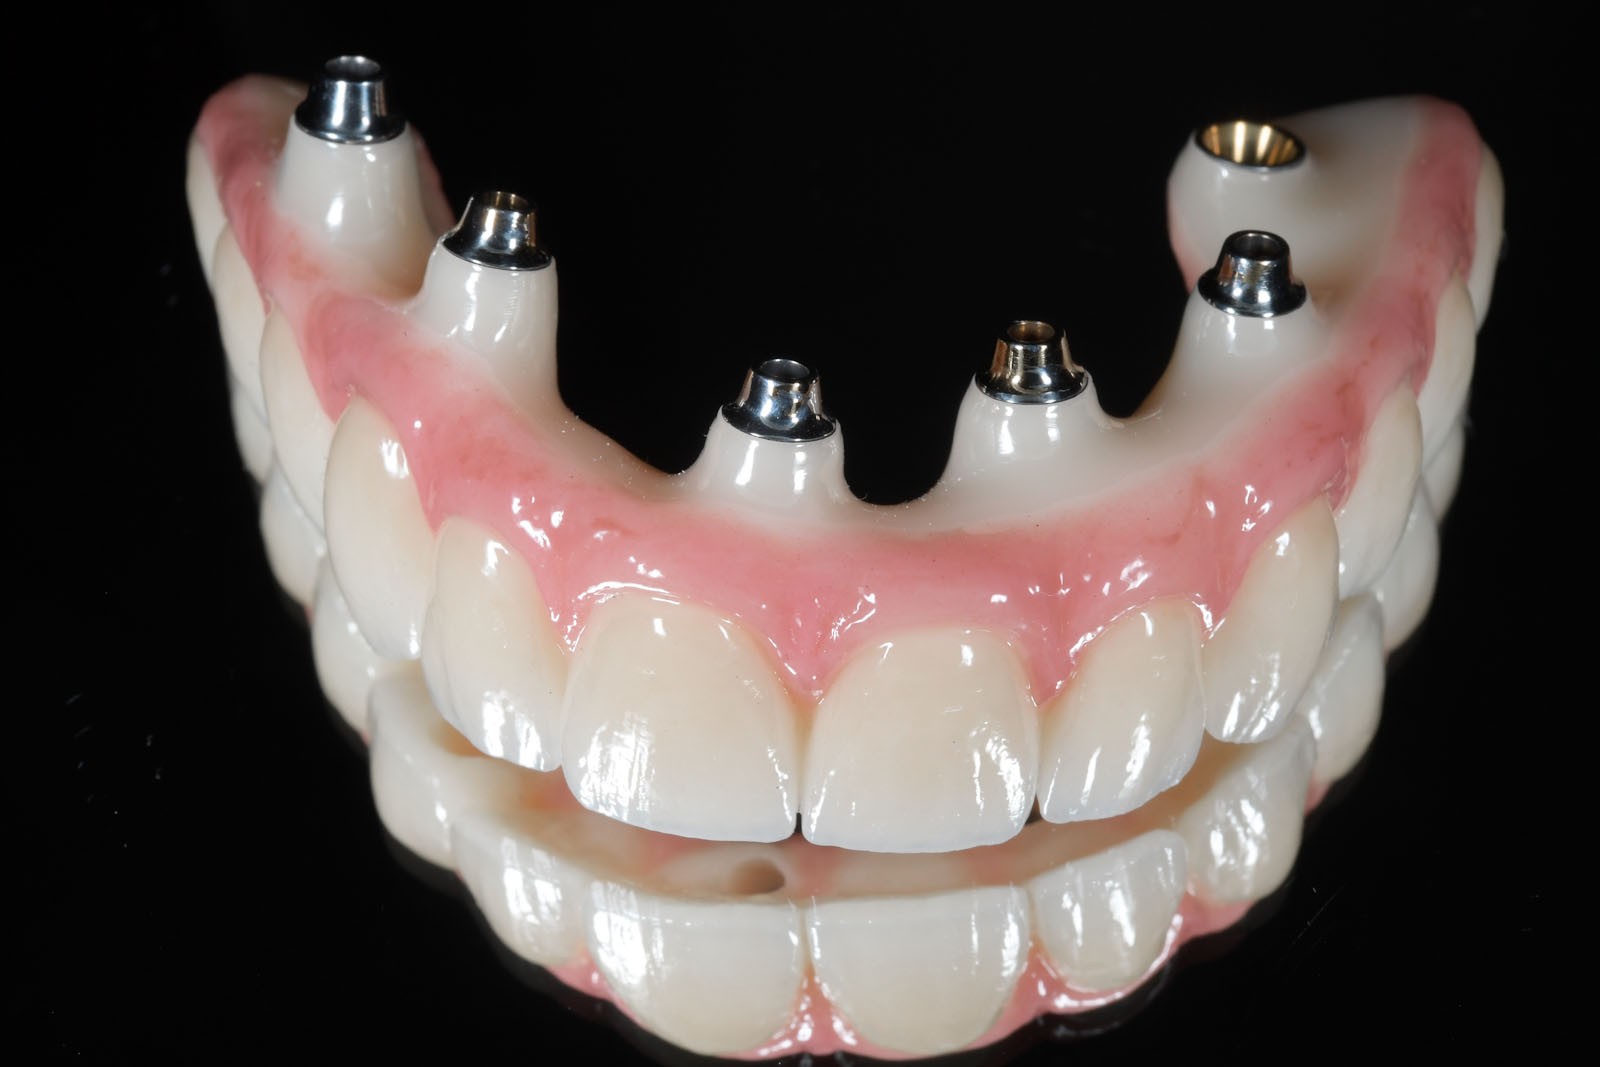

Uzupełnienia stałe w sposób permanentny, lecz nie rozłączny montowane są na zębach lub implantach w jamie ustnej pacjenta. Do stałych uzupełnień zaliczamy wkłady koronowo-korzeniowe, wkłady koronowe, licówki, korony i mosty oraz uzupełnienia stałe oparte na wszczepach śródkostnych.

Komfortową alternatywą dla mostu jest rehabilitacja implanto-protetyczna, zarówno w przypadku braku pojedynczego, jak i większej liczby zębów. Implantacja wskazana jest w szczególności, gdy zęby sąsiadujące z luką są zdrowe, nie leczone kanałowo, a podłoże kostne spełnia warunki dla implantacji. Pozwala to uniknąć szlifowania zębów filarowych stojących obok luki, a przyszła konstrukcja protetyczna najczęściej nie uwzględnia przęsła mostu, które może sprawiać trudności w utrzymaniu higieny jamy ustnej. Korony i mosty wsparte na implantach przenoszą siły powstające w procesie żucia przez osie implantów wszczepionych w kość. Tworzy to układ działania sił najbardziej zbliżony do fizjologicznych warunków jamy ustnej z uzębieniem. Jest on optymalny dla zdrowia i zachowania tkanki kostnej. W ten sposób przenoszona siła powoduje wzmocnienie kości, nie zaś jej resorpcję, czyli zanik.

W związku z ich użytkowaniem skala komfortu dla pacjenta zależy od tego, czy są to ruchome protezy Overdenture oparte jedynie na implantach, które poprawiają stabilizację protez zębowych, czy też na stałe mocowane na wszczepach mosty. W ślad za wyborem rodzaju mocowania protez idzie jakość odbudowy protetycznej. Protezy Overdenture są wykonane z materiału kompozytowego lub akrylu, natomiast mosty są wykonane z ceramiki.